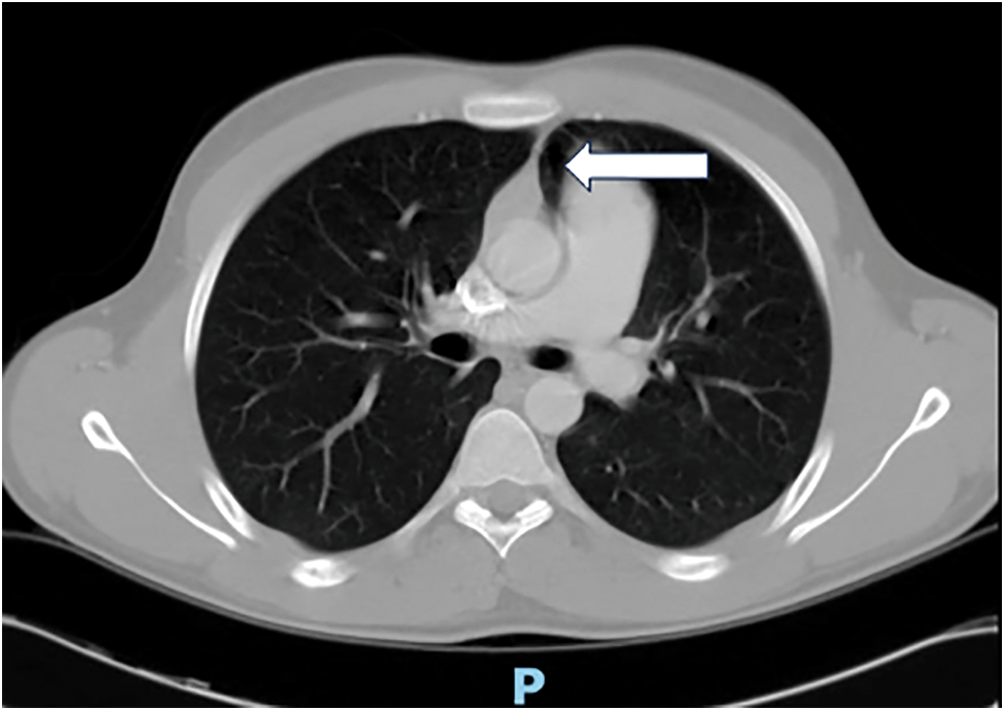

See Figs. 1–3 for a description of the diagnostic criteria.

Figure 1: Computed tomography scan showing a tongue of lung tissue between the aorta and main pulmonary artery (white arrow). This is typical of CAP. The aortopulmonary window is usually bounded by pericardium and contains fat (previously unpublished image belonging to the authors)